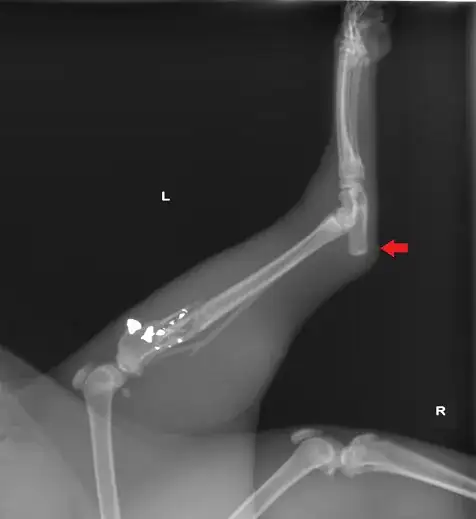

[The particular leg in the diagram] represents the back leg of a dog/cat, the heel is extended on the blackleg to give the animal more power when jumping.

This is good for pouncing predators, but also the only practical way large animals can jump with any distance, such as horses, which only have the pivot on the back leg and have pillar legs on the front (the bones are inline, there is no modified heel pivot location).